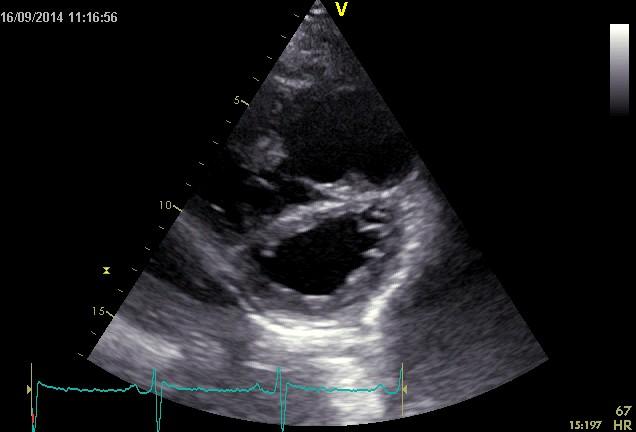

Echokardiografie: LEVÁ KOMORA bez dilatace a hypertrofie, s normální systolickou funkcí a regionální kinetikou kromě D shape, EF LK 55-60%. Diastolická funkce: porucha relaxace LK. PRAVÁ KOMORA FAC PK 18%, TAPSE 13 mm, Vt 9 cm/s, dilatace a hypertrofie PK, těžká prekapilární PH, odhadovaný PASP 90 mmHg, MPAP 55 mmHg, malý perikardiální výpotek

Echokardiografie: LEVÁ KOMORA bez dilatace a hypertrofie, s normální systolickou funkcí a regionální kinetikou kromě D shape, EF LK 55-60%. Diastolická funkce: porucha relaxace LK. PRAVÁ KOMORA FAC PK 19%, TAPSE 17 mm, Vt 9 cm/s, dilatace a hypertrofie PK, těžká prekapilární PH, odhadovaný PASP 130

mmHg, perikardiální výpotek